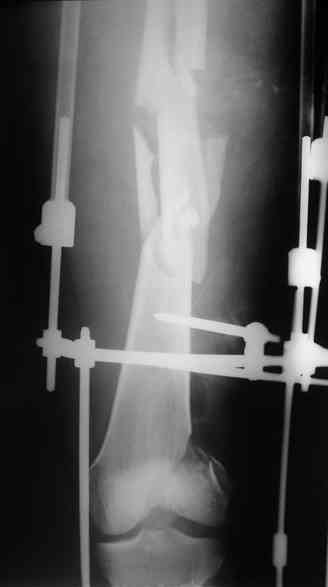

Перелом диафиза и мыщелка бедра |

Молодой человек 28 лет, травма внутрисалонная при ДТП 19.10.2006.

При поступлении дренирован правосторонний гемопневмоторакс, перелом левой бедренной кости (открытый IIБ по Каплану-Марковой) стабилизирован аппаратом внешней фиксации. В настоящее время гемопневмоторакс купирован, рана на левом бедре заживает первично, больной адекватен, активен. Хотелось бы услышать мнения по ведению данной патологии.